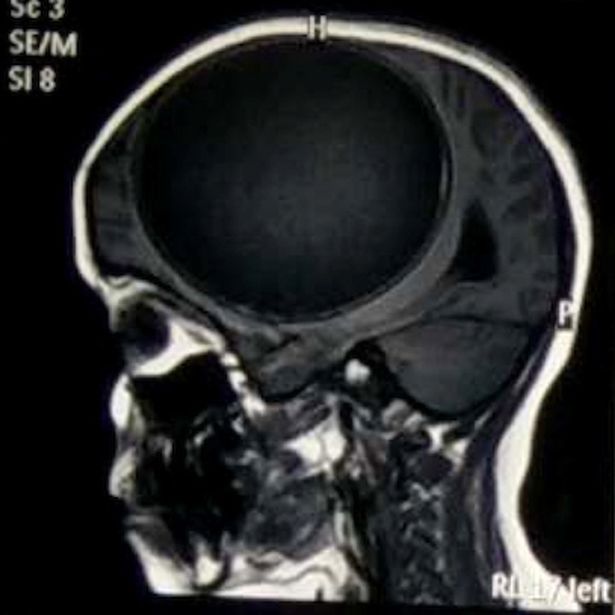

Sık sık nöbet geçiren ve bir tarafı felç olan 12 yaşındaki kızın hastalığının sebebi doktorları şoke etti. 12 yaşındaki hintli nita juggi sürekli nöbet geçiriyor ve son 12 aydır vücudunun bir tarafı felçli haldeydi.

Doktora başvurduktan sonra yapılan çeşitli tetkikler sonrasında küçük kızın beyninin yarısını kaplayan tenya yani bağırsak kurdu larvalarından kaynaklı merkezi sinir sisteminde sistiserkoz teşhis edildi.

Bir bağırsak kurdunun larvasının sebep olduğu kist greyfurt büyüklüğünde ve her an patlayıp ölüme sebep olabilecek boyutlardaydı. başarılı bir ameliyatla beynindeki kist alınan kız şuan iyileşme sürecinde.